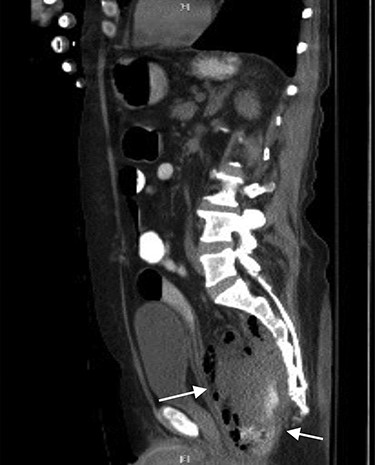

CT abdomen and pelvis showed a rectal perforation with perirectal pelvic inflammatory soft tissue/phlegmon containing air-fluid level that infiltrated into the presacral space extending up through the sciatic notch into the right gluteus medius and minimus muscle (Figs 1 and 2). Chronic inflammatory changes of the transverse colon and left colon were also present. The patient was taken to the operating room (OR) for examination under anesthesia. A flexible sigmoidoscopy was passed up into the distal descending colon, which showed discontinuous areas of ulcerated mucosa with cobble-stoning notable for active Crohn’s disease and a diffuse pseudomembrane reminiscent of C. difficile colitis (the negative C. difficle assay). A rectal perforation was noted just above the dentate line. The incision was enlarged and the presacral space was entered with a flexible sigmoidoscope. There was extensive necrosis of the presacral tissue with copious amounts of purulent fluid. The abscess was evacuated, and all loculated fluid collections were drained. The cavity was then irrigated via the sigmoidoscope. Once satisfactory drainage was achieved, a Malecot catheter was then inserted through the rectal perforation into the presacral space. A laparoscopic diverting loop ileostomy was then created to allow for healing.

CT sagittal view showing contrast (white) entering the lumen of presacral abscess and rectus abdominis muscle pushed anteriorly.